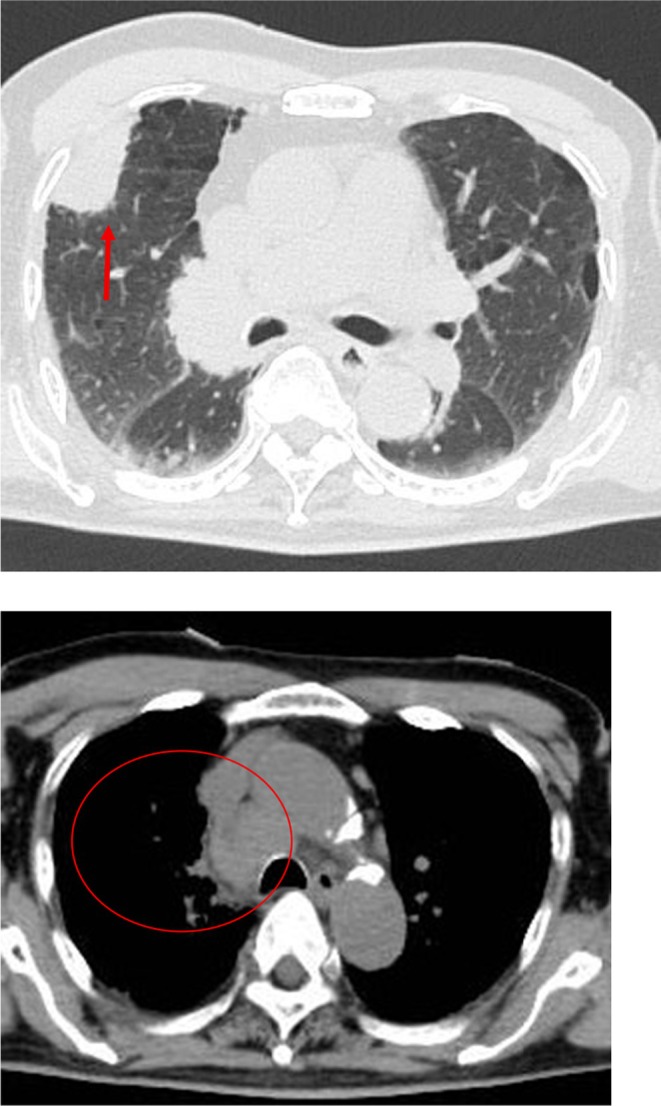

Case presentation: An 80-year-old male with no psychiatric history presented with flu-like symptoms, followed by the acute onset of neuropsychiatric symptoms, including pressured speech, agitation, memory impairment, and abnormal behavior. Autoimmune encephalitis was suspected due to mildly elevated cerebrospinal fluid (CSF) white cell count and a mass in the right upper lung detected by whole-body computed tomography (CT) on the first day of hospitalization. High-dose intravenous corticosteroids were administered on Day 1, resulting in prompt and sustained improvement in symptoms. CSF was later confirmed positive for anti-NMDAR antibodies, and a bronchoscopy biopsy of the pulmonary mass diagnosed SCLC. The patient recovered without neurological deficits and was discharged in stable condition on hospital Day 30.